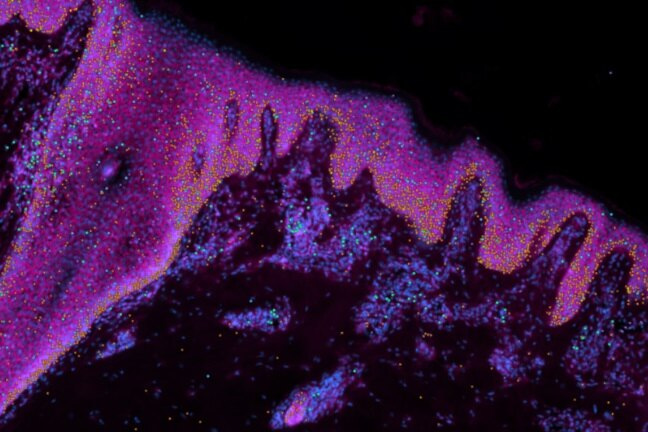

Исследователи из Кембриджского института стволовых клеток впервые создали подробный атлас кожи человека до рождения, чтобы понять, как формируется кожа и что происходит при ее заболеваниях. Ученые считают, что исследование поможет выработать клинические методы, позволяющие залечивать раны без шрамов и выращивать волосяные фолликулы, что может помочь при облысении.

Исследователи из Кембриджского института стволовых клеток впервые создали подробный атлас кожи человека до рождения, чтобы понять, как формируется кожа и что происходит при ее заболеваниях.

Эти знания могут быть использованы для создания новых волосяных фолликулов в регенеративной медицине и при пересадке кожи пострадавшим от ожогов. В исследовании, опубликованном в журнале Nature, команда создала «мини-орган» кожи, обладающий способностью выращивать волосы.

Используя органоид, ученые показали, что иммунные клетки играют важную роль в восстановлении кожи без рубцов. Это может найти клиническое применение для предотвращения образования рубцов после операций или заживления ран без рубцов.

В рамках проекта «Атлас клеток человека», в котором отображаются все типы клеток человеческого организма, исследователи представили молекулярный «рецепт» для создания кожи и новую органоидную модель для изучения врожденных кожных заболеваний.